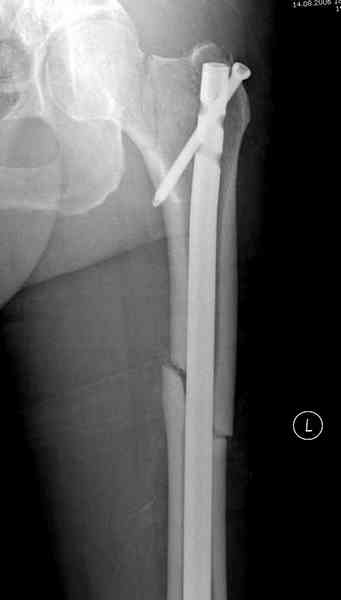

В операционной спереди гвоздя провел два 6.5 мм каннулированных шурупа, также через проксимальное отверстие антеградного гвоздя удалось провести шуруп.

Здесь представлены снимки больного 65 лет, поступившего с диагнозом перелом

бедра после автоаварии.

В первый же день произведено антеградное штифтованием DePuy Trochanteric Nail.

На второй день (7) обнаружен пропущенный перелом,

и проведены шурурпы через и спереди штифта без удаления.

Послеоперационные снимки